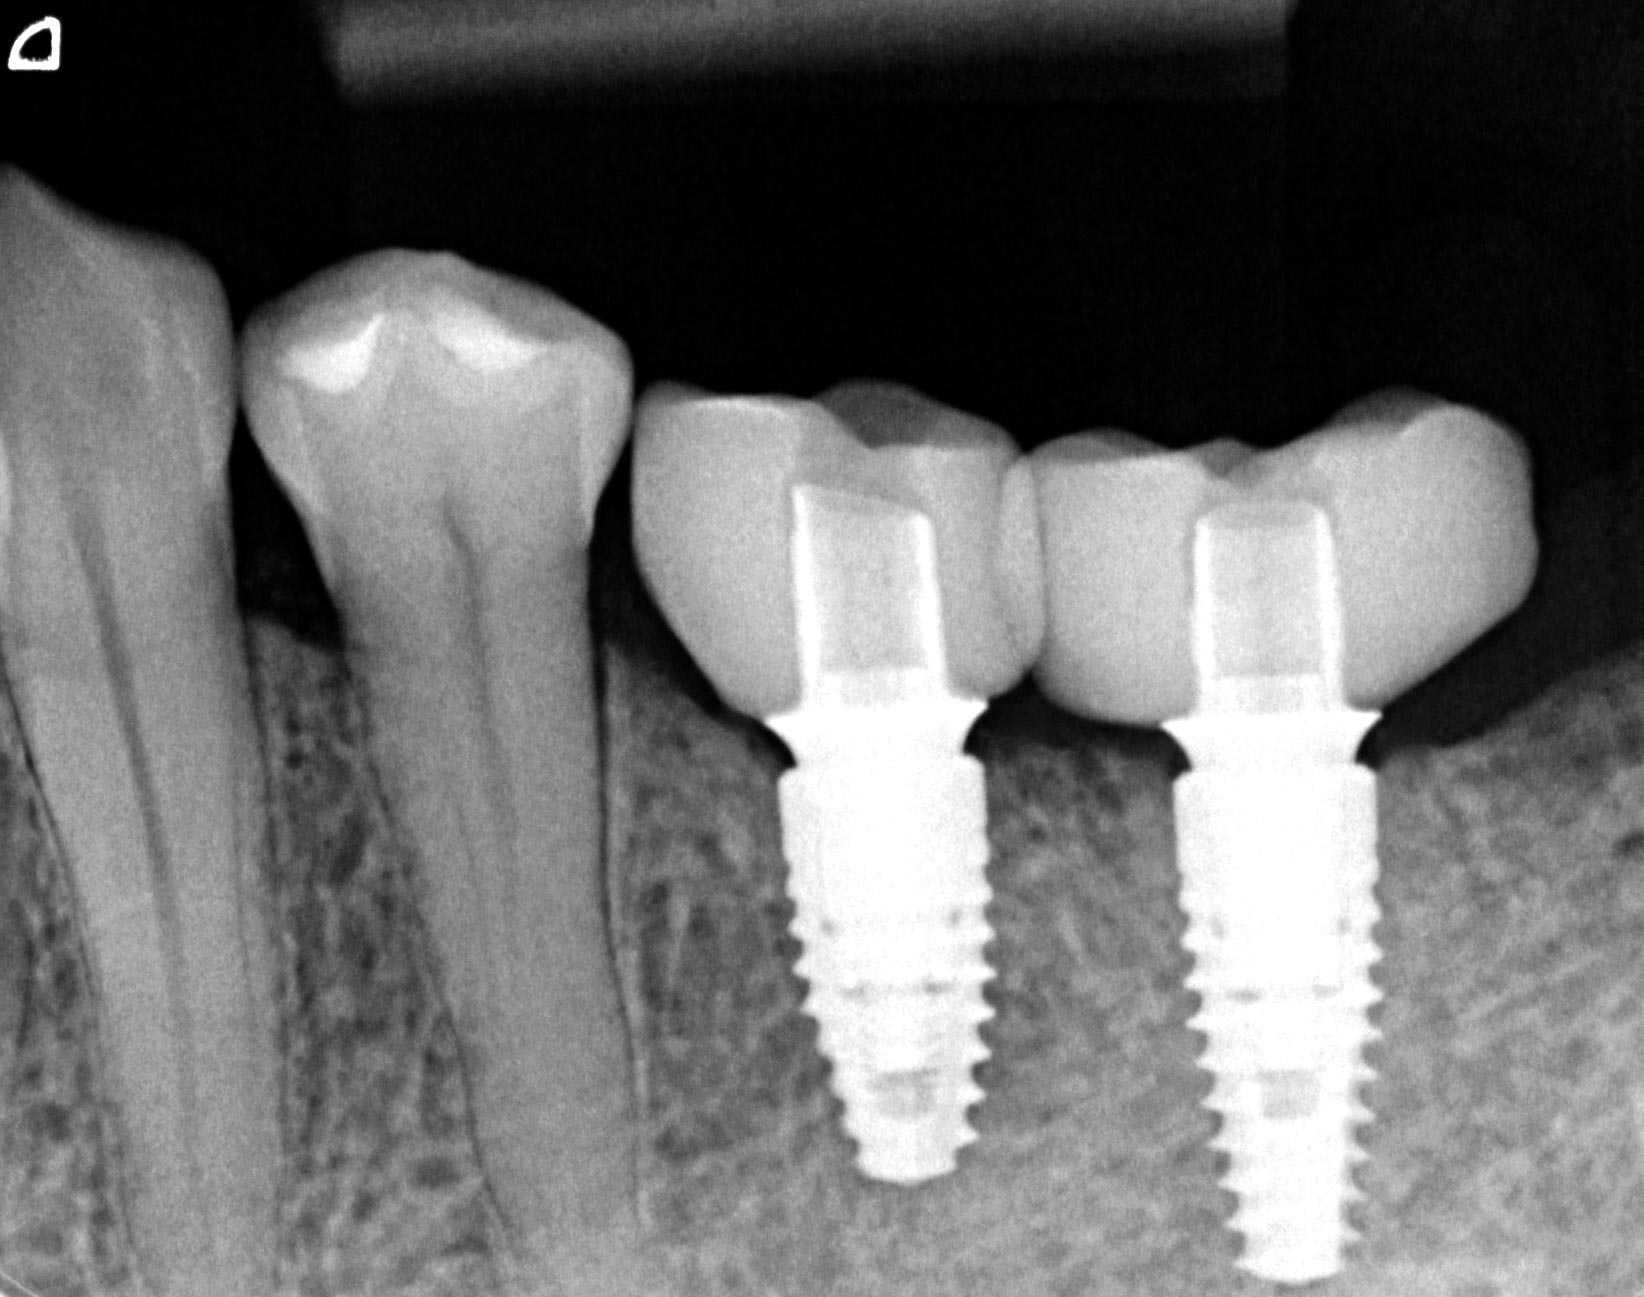

Preoperative situation – Maxillary defect in area 14-16 (loss of implant 16 due to periimplantitis, tooth 14 extracted recently and area 15 already edentulous for a while)